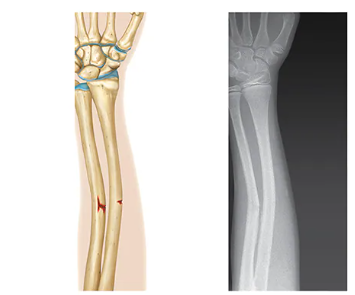

Compression